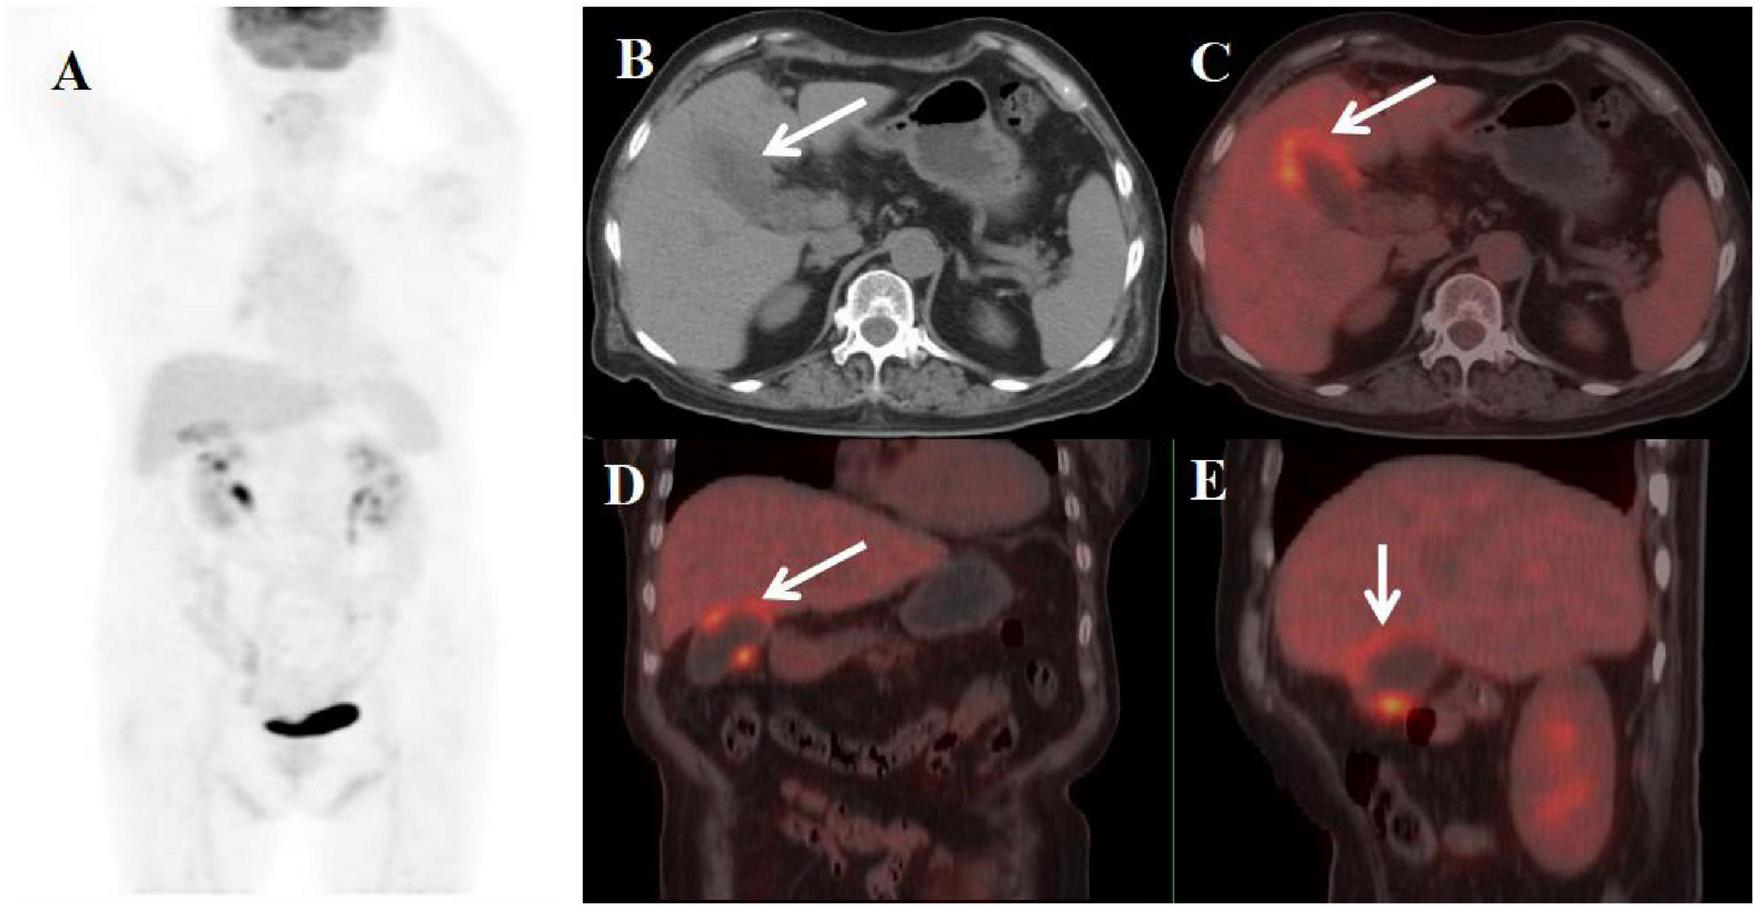

A 59-year-old female presented with abdominal pain for two weeks. Physical examination revealed a positive Murphy’s sign. The patient had a history of breast cancer surgery. Initial laboratory findings demonstrated moderate leukocytosis (WBC 12.50 × 109/L) with neutrophilic predominance (81%). Additionally, elevated inflammatory markers were observed, including C-reactive protein (CRP: 13 mg/L) and a mild increase in carbohydrate antigen 19-9 (CA19-9: 70.51 U/mL). All other tumor markers were within normal limits. Abdominal ultrasonography and MRI performed at an outside hospital demonstrated gallbladder wall thickening with multiple intraluminal gallstones. Given the clinical presentation, gallbladder malignancy could not be excluded, prompting referral to our institution for PET/CT evaluation. The PET/CT scan demonstrated an enlarged, adherent gallbladder with diffusely irregular wall thickening (maximum 12 mm) containing intramural hypodense nodules. The lesion showed intense FDG avidity (SUVmax 19.8) while maintaining mucosal integrity, though with loss of the normal hepatobiliary interface. Additional findings included inflammatory changes in pericholecystic fat and enlarged retroperitoneal lymph nodes (Figure 2). These features were initially interpreted as consistent with advanced gallbladder carcinoma with hepatic invasion and nodal metastasis. The patient subsequently underwent definitive surgical management including open cholecystectomy with partial hepatectomy. Final histopathological examination established the diagnosis of XGC, characterized by the hallmark findings of foamy histiocyte aggregates, chronic inflammatory infiltrates, and cholesterol clefts without evidence of malignancy.

Figure 2. Female, 59 years old. (A) (whole body MIP), (B, C) (Axial CT and fused axial PET-CT), (D, E) (Coronal CT and fused coronal PET-CT), and (F, G) (Sagittal CT and fused sagittal PET-CT). 18F-FDG PET/CT Imaging Findings: The gallbladder appears enlarged and adherent, demonstrating diffuse irregular wall thickening (maximum 12 mm) with intramural hypodense nodules (B, D, F, arrow ↑). Significant FDG uptake (SUVmax 19.8) was observed in the lesion, which preserved mucosal continuity despite disruption of the typical hepatobiliary interface (C, E, G, arrow ↑). Accompanying features comprised inflammatory infiltration of pericholecystic adipose tissue and enlargement of retroperitoneal lymph nodes.